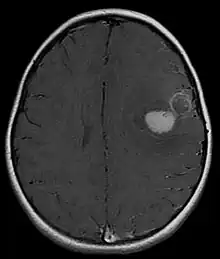

Tumeur neuroectodermique primitive du système nerveux central

Une tumeur neuroectodermique primitive (PNET) du système nerveux central fait habituellement référence à une tumeur neuroectodermique primitive supratentorielle :